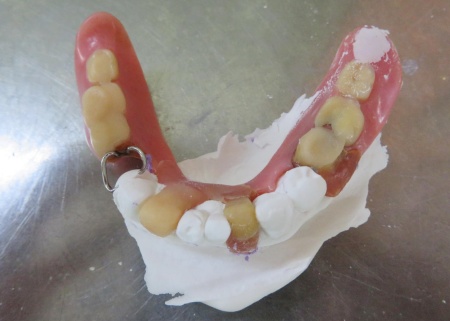

治療前

治療中

クラスプを固定する場所を削りました